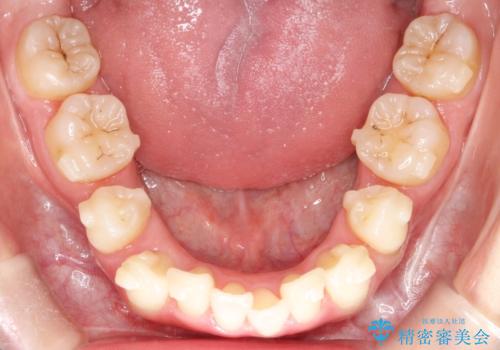

【抜歯インビザ】前歯の凸凹をなおしたい

- 前歯の凸凹を主訴に来院されました。

前歯はあまり下げる必要がなかったため、上下左右の第二小臼歯抜歯を行う治療計画としました。

途中、臼歯の近心傾斜を認めましたが、追加アライナーを使用することでリカバリーを行いながらインビザラインのみで治療を完了することができました。